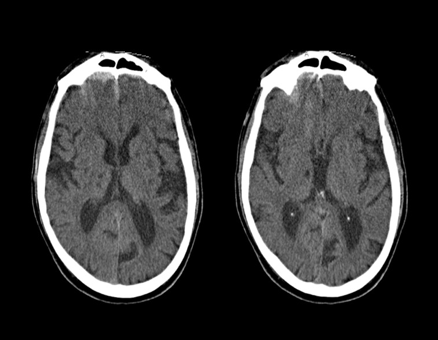

Chronic lacunar infarcts

CT head (without contrast; axial plane)

Multiple, very small, sharply-demarcated hypodense lesions are present in the basal ganglia, left internal capsule , and right thalamus . Additionally, there is diffuse cerebral atrophy with prominence of the sulci and ventricles.